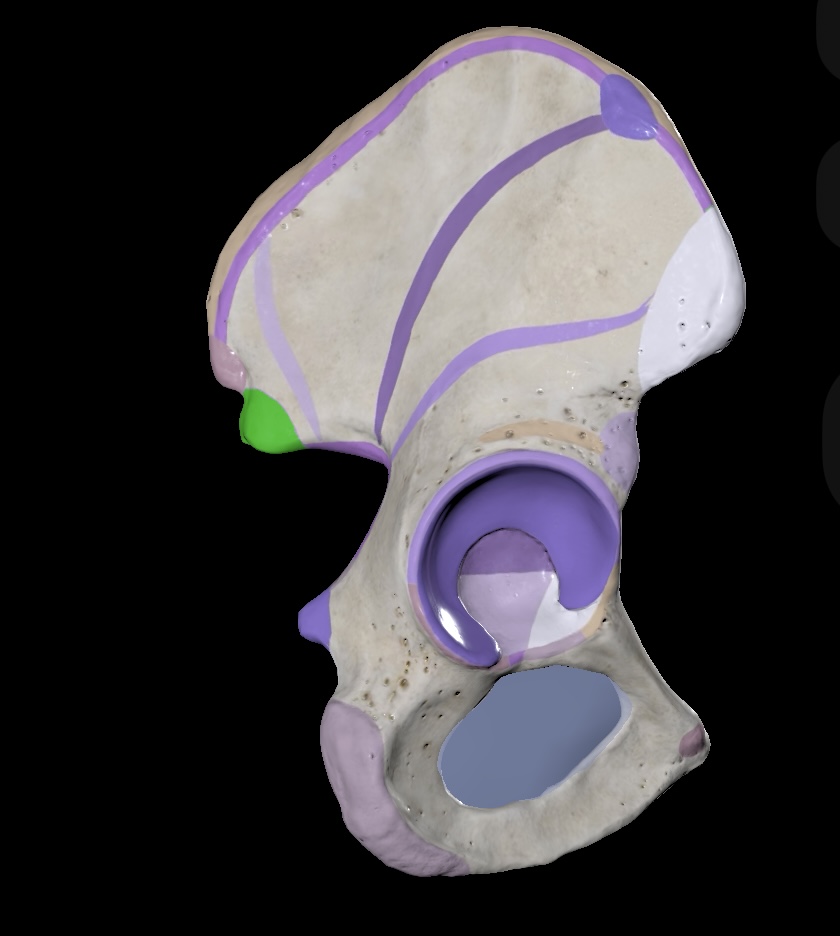

Illium

Ischium

Pubis

Ischial Spine of Ischium

Iliac Tuberosity of Illium

Anterior Superior Iliac Spine

Anterior Inferior Iliac Spine

Posterior Superior Iliac Spine

Posterior Inferior Iliac Spine

Iliac Crest

Acetabulum